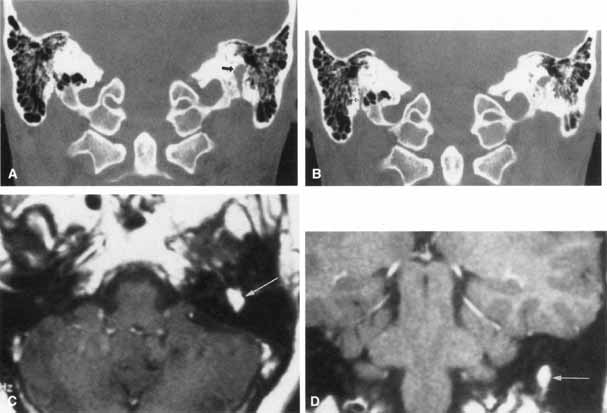

On CT scan, acoustic neuromas may be seen as enhancing masses in the internal auditory canal or cerebellopontine angle. For smaller tumors, gadolinium-enhanced MRI may be very helpful. On T1-weighted gadolinium images, neuromas may appear as uniformly enhancing masses, effacing the brain stem and cerebellum with extension into the internal auditory meatus or canal. On T2-weighted images these lesions appear hyperintense (Fig. 15).89 Treatment usually consists of microsurgical excision with the use of techniques that may provide complete removal of tumor and preservation of the facial nerve. Intraoperative facial nerve monitoring during acoustic neuroma surgery may improve the preservation of facial nerve function.90,91 Spontaneous recovery of facial function usually begins by 3 to 4 months after surgery and is typically finished by 1 year. Those palsies persisting beyond one year are likely to be permanent.92

Fig. 15 Magnetic resonance imaging of acoustic neuroma. A. Coronal section through pons showing bilateral acoustic neuromas in a patient with neurofibromatosis. B. Normal study of same area.

The facial paralysis associated with facial nerve neuromas usually has a gradual onset, but it may be more rapid, simulating idiopathic facial paralysis. Indeed, the pareses may fluctuate or may be associated with hemifacial spasm. In some cases, hearing loss precedes the onset of facial weakness, thereby simulating an acoustic neuroma.93 CT scan typically shows a uniformly enhancing mass in the fallopian canal. T2-weighted MRI images may show a hyperintense mass in the facial canal89 that enhances with gadolinium on T1-weighted images (Fig. 16). The ultimate diagnosis of facial neuroma requires surgical exploration and biopsy. Biopsy usually results in facial paralysis. This possibility should be discussed with the patient before surgery. Facial function recovery after resection of tumor and grafting, although never normal, may include restored tone, symmetry, and weak voluntary movement. The more facial function present before surgery, the better the results with grafting. This observation must be shared with the patient, because he or she might elect to wait until facial function is lost before consenting to surgical removal. When the tumor is located eccentrically, removal is possible with preservation of facial function.94

Fig. 16 Patient with facial neuroma. A. Coronal CT scan demonstrating enlarged stylomastoid foramen and facial nerve mass (arrow). B. Note size of canal in Figure A (black arrow) compared with normal sized canal (open arrow). C. Axial MRI scan showing an enhancing mass of tympanic segment (arrow). D. Coronal gadolinium-enhanced MRI section demonstrating same mass in mastoid segment (arrow).